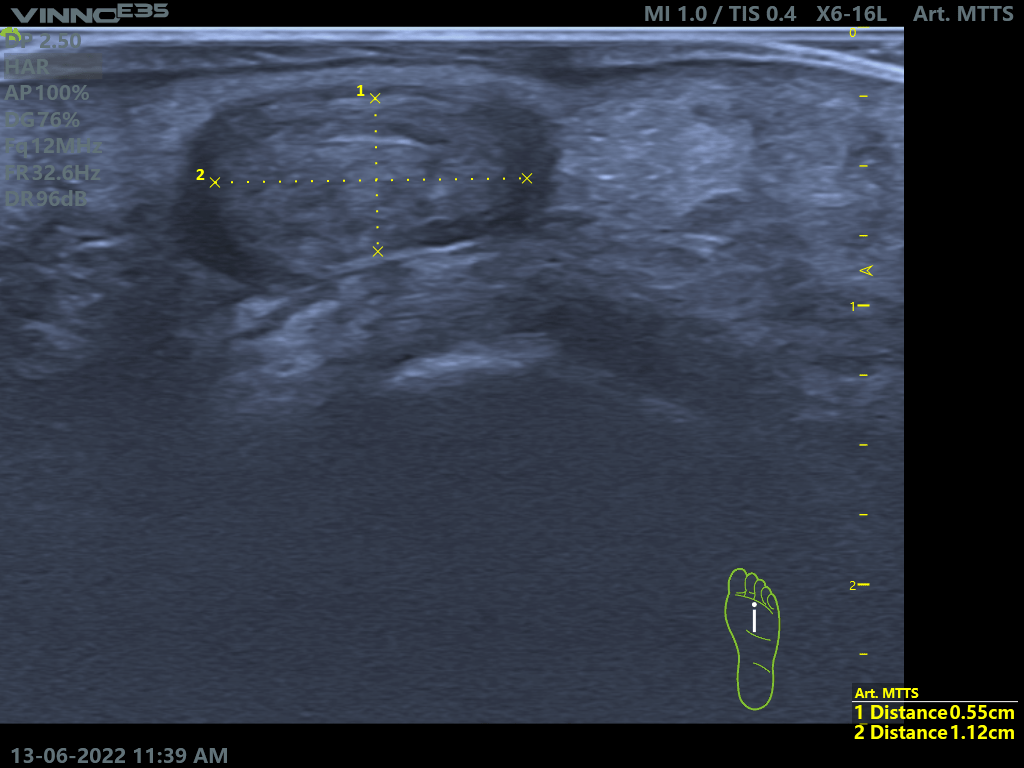

La infiltración ecoguiada es una técnica para tratar la patología articular, muscular, ligamentosa, del tendón y de la fascia mediante la introducción de sustancias medicamentosas con ayuda de un ecógrafo en tiempo real, con una precisión de practicamente en 100%, en el tejido o estructura lesionada. Gracias al uso del ecógrafo en las infiltraciones podemos acceder a la zona lesionada sin dañar otras estructuras durante el recorrido de la aguja y maximizar la acción farmaceutica, ya que el medicamento va solo a la zona dañada, lo que aumenta la probabilidad de éxito del tratamiento.

Por lo tanto, ayudará a aliviar el dolor, reducir la inflamación o mejorar la movilidad en enfermedades como artritis, tendinitis, fasciopatias o bursistis.

Casos prácticos